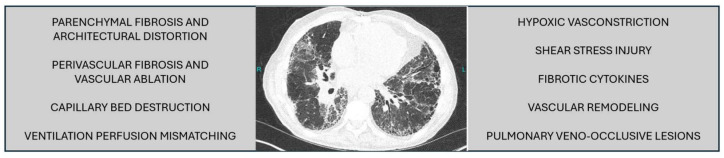

世界卫生组织(WHO)根据各疾病状态的病理生理和特点,将肺动脉高压疾病分为五类。已经开发了几种靶向治疗药物来对抗世卫组织第1组肺动脉高压的血管重塑,然而,在其他世卫组织组中寻找治疗方案的成果较少。在这篇综述中,我们关注肺动脉高压和间质性肺病(PH-ILD)患者的治疗选择。针对WHO第1组PAH治疗的研究在很大程度上未能改善PH-ILD患者的功能、血流动力学、氧合、生活质量或生存率。相比之下,在一项名为INCREASE的安慰剂对照研究中,吸入曲前列尼的PH-ILD患者在主要终点(6分钟步行距离)中显示出31米的安慰剂校正改善。与安慰剂相比,吸入曲前列替尼治疗还与临床恶化时间的改善、潜在肺部疾病的恶化减少、n端前b型利钠蛋白(NT-proBNP)水平的降低以及强迫肺活量的改善相关。在这篇综述中,我们还阐述了目前对导致PH-ILD的病理生物学的理解,重点是血管生物学中更新的信号通路和介质的作用,这可能会扩大治疗选择。在强调早期发现和诊断重要性的同时,强调了早期发现和诊断的战略和创新。概述了一种治疗PH-ILD的整体和协作方法,包括各种辅助措施和考虑患者报告的结果数据,以改善疾病管理结果。

Pulmonary hypertensive diseases have been classified by the World Health Organization (WHO) into five groups based on the pathophysiology and characteristics of each disease state. Several targeted therapeutic agents have been developed that combat the vascular remodeling in WHO Group 1 pulmonary arterial hypertension, however, the search for treatment solutions in other WHO Groups has been less fruitful. In this review, we focus on therapeutic options for patients with pulmonary hypertension and interstitial lung disease (PH-ILD). Investigations of targeted WHO Group 1 PAH therapies have largely failed to improve functional capacity, hemodynamics, oxygenation, quality of life, or survival in PH-ILD. In contrast, inhaled treprostinil was shown effective in the INCREASE Trial, a placebo-controlled study in which patients with PH-ILD treated with inhaled treprostinil demonstrated a 31-meter placebo-corrected improvement in the primary endpoint, 6-minute walk distance. Treatment with inhaled treprostinil was also associated with improvement in time to clinical worsening, fewer exacerbations of underlying lung disease, decrease in N-terminal pro-B-type natriuretic protein (NT-proBNP) levels, and improvement in forced vital capacity compared to placebo. In this review, we also elaborate on the current understanding of the pathobiology leading to PH-ILD with emphasis on the role of newer signaling pathways and mediators of vascular biology that may expand treatment options. Strategy and innovations for early detection and diagnosis are highlighted while underscoring the importance of early detection and diagnosis. A holistic and collaborative approach to the treatment of PH-ILD is outlined including a variety of adjunctive measures and the consideration of patient-reported outcome data in order to improve disease management outcomes.